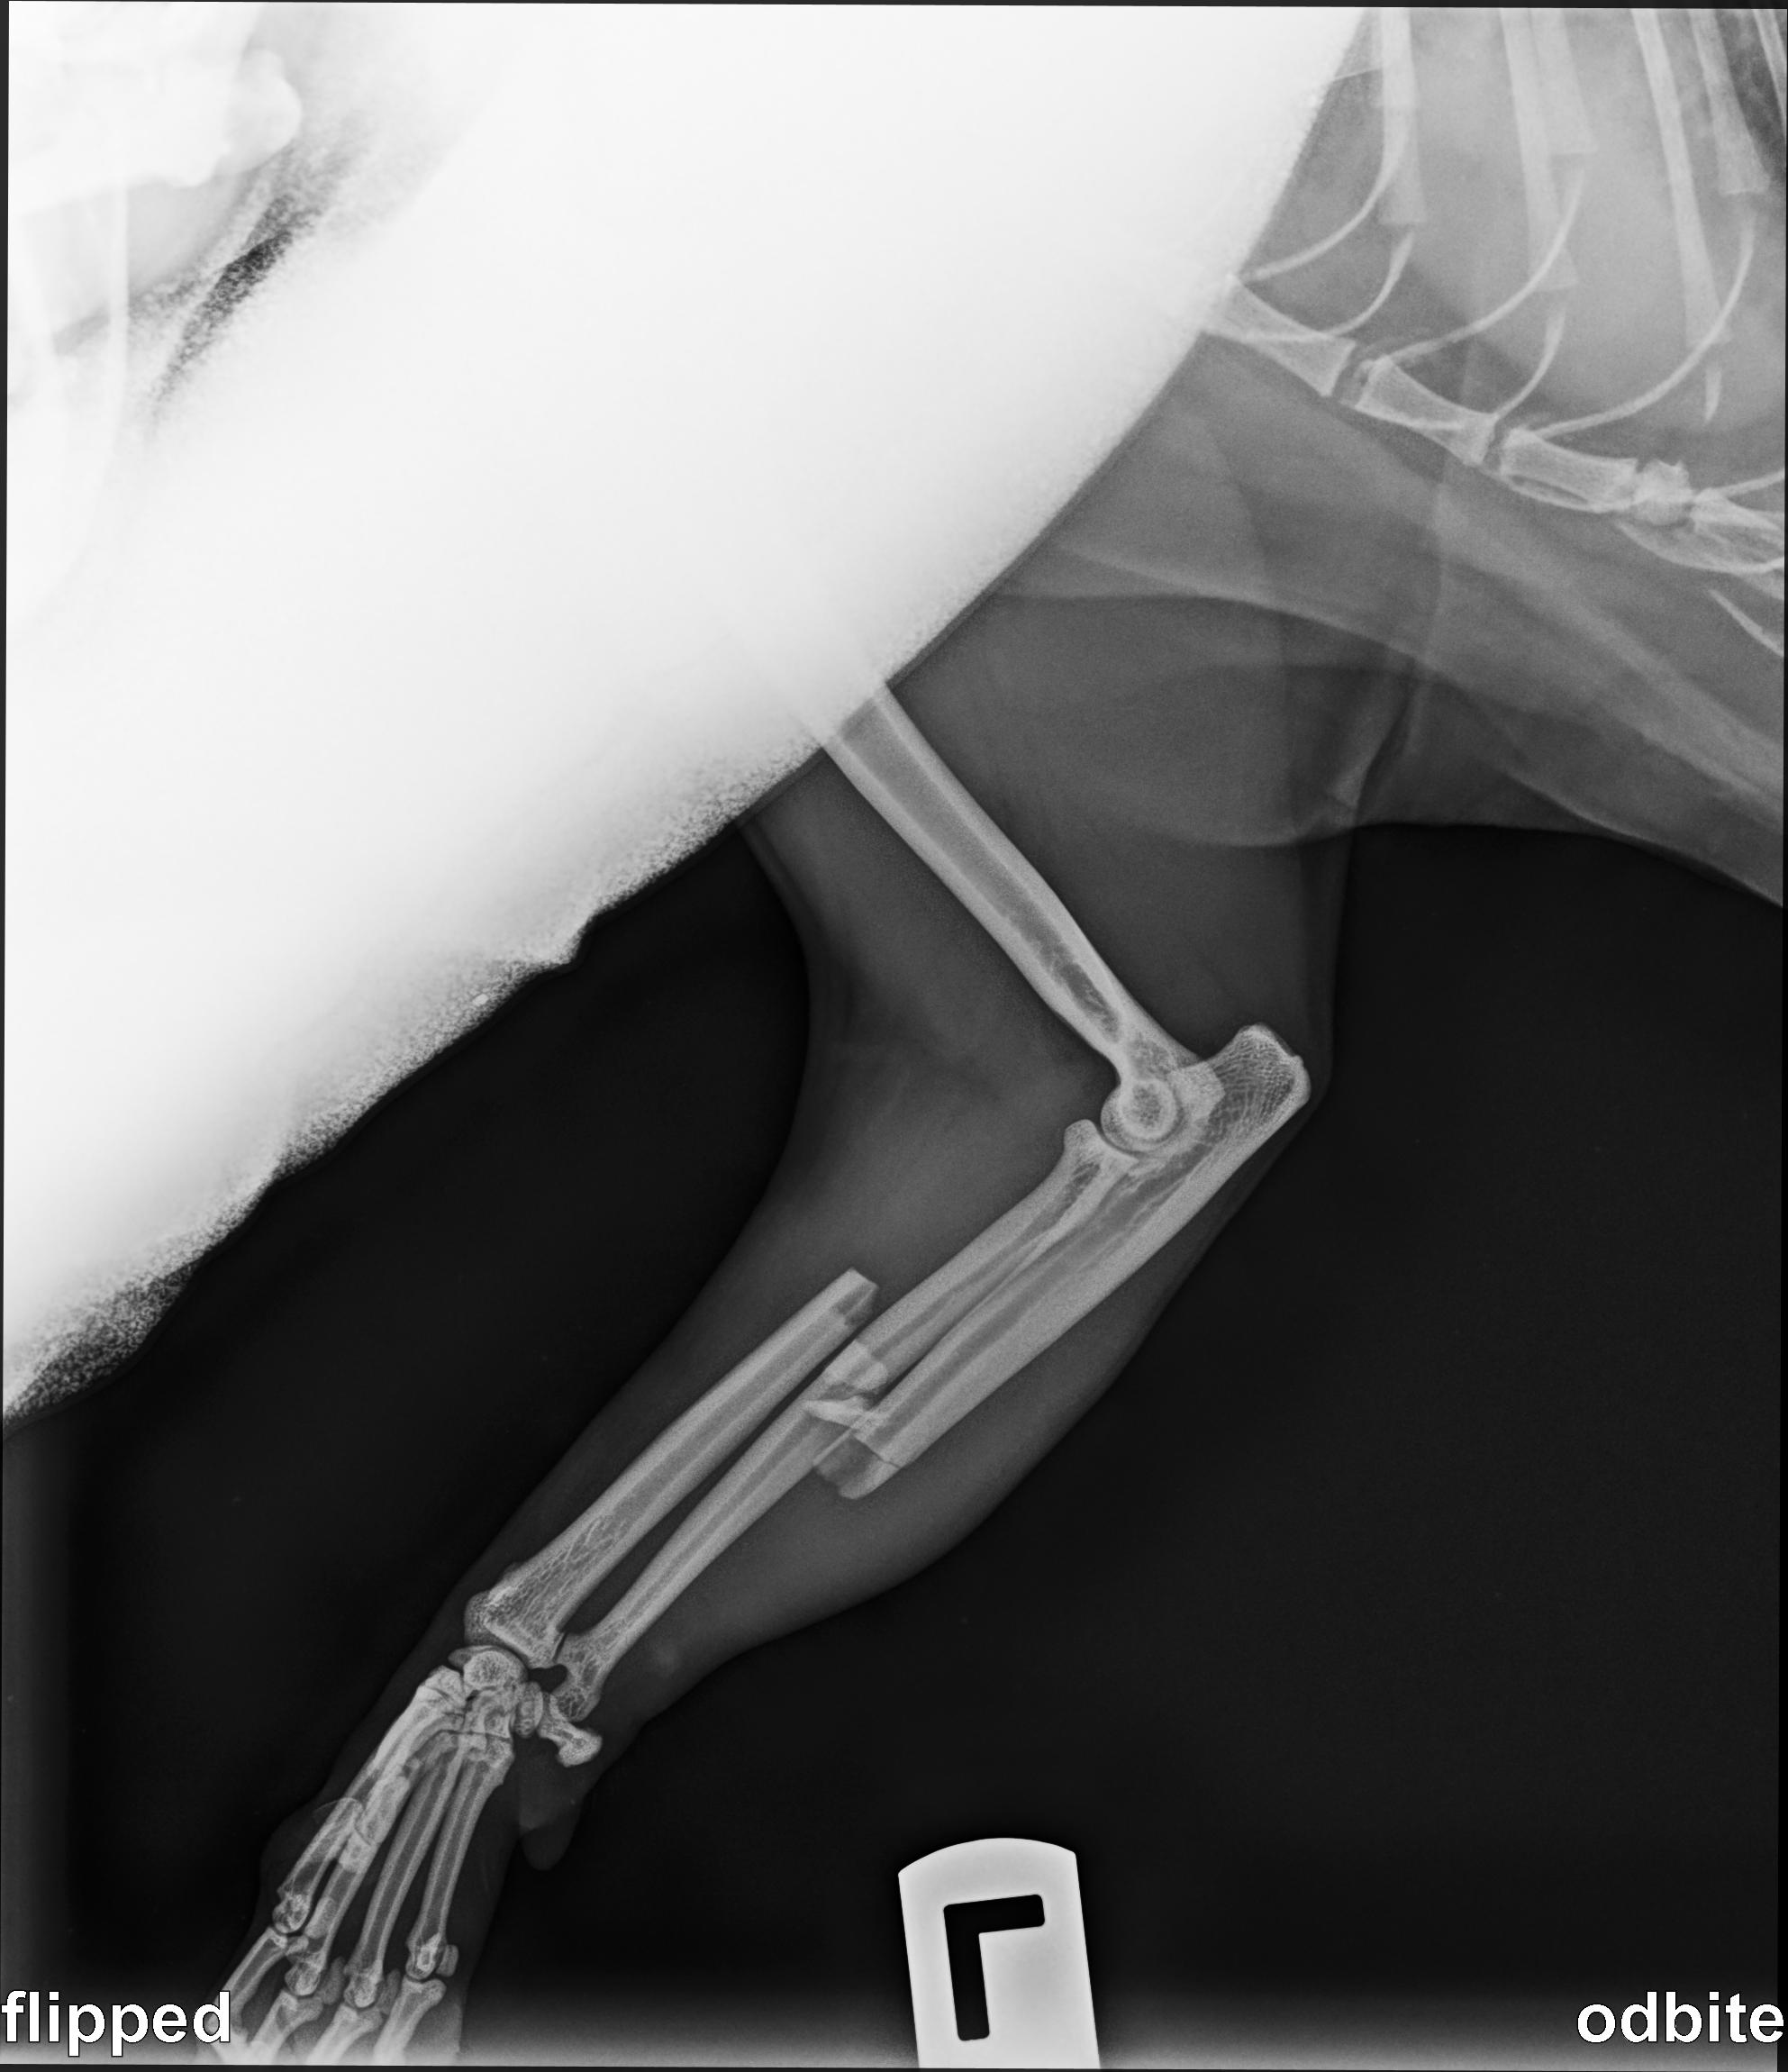

Benek je mamin kocúr a minulé leto sa mu stala hrozná nehoda - bol rozdrvený v automatickej bráne na príjazdovej ceste.

Výsledkom boli dve silno zlomené labky, z ktorých jedna bola aj vykĺbená.

Najprv potreboval korekčnú operáciu vykĺbeného kĺbu. Potom sa jedna z jeho rán infikovala, čo si vyžiadalo antibiotickú liečbu. Najnovšie sa mu zlomil jeden z drôtov, ktoré držali kosti pohromade, čo znamenalo, že musel podstúpiť ďalšiu operáciu.